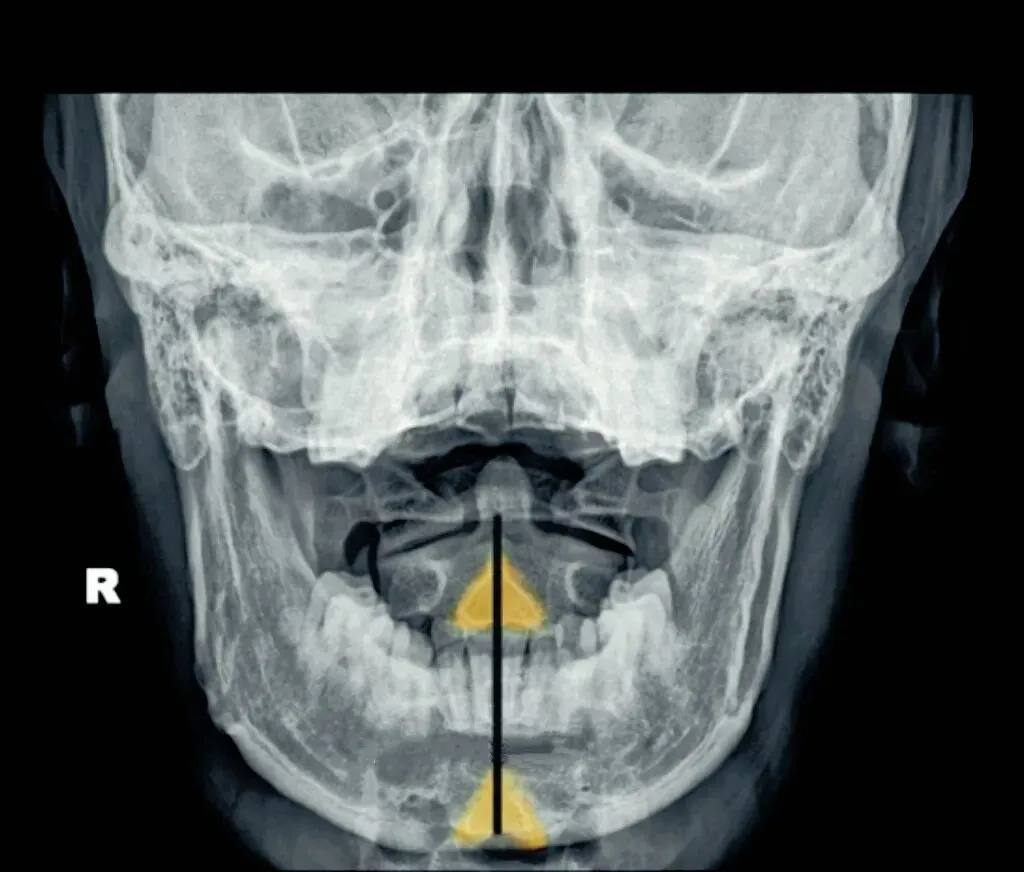

十张口是指寰枢椎的结构和位置关系,我们主要观察寰齿间隙和寰枢关节间隙及寰椎侧块的大小,来判断寰枢关节有无脱位的情况。

首先是寰齿间隙,如果枢椎与颈三的棘突位于同一条直线,

那么寰齿间隙哪边宽,就代表寰椎向哪边发生了侧方移位。

如果不在一条直线上,那就代表枢椎也有侧向的移动或旋转。

接下来是寰枢关节间隙,也称寰枢外侧关节,主要看两侧间隙是否等大,

如果一边宽一边窄,就代表寰椎向窄的一方发生了侧向倾斜。

再下来看寰椎侧块的大小,正常情况下侧块两边的宽度是等大的,

如果哪边侧块变大,就代表哪边的侧块向前方发生了旋转。